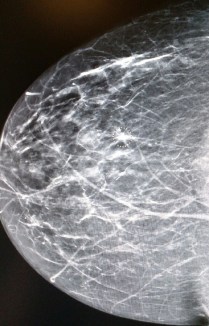

I could see from the displayed previous image of my mammogram displayed on the monitor that they were focusing on a tiny area that just looked like a blur to me. The young lady was gentle as she manipulated my right breast into the correct position for each image.

The radiologists words were reassuring as she informed me the spot they needed more information about was just a tiny little tangle of blood vessels that wasn’t very clear in the mammogram. She reminded me that I have fibrous breasts and told me it would be a good idea for me to continue getting the 3D mammograms, my next being needed in a year.